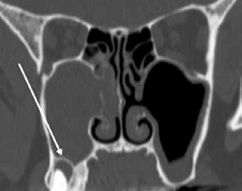

Bei anhaltender klinischer Symptomatik nach erfolgter Zahnbehandlung sollten gegebenenfalls eine rhinochirurgische Behandlung zur Verbesserung der maxillären Clearance und Entfernung des entzündlichen Débris aus der Höhle über einen erweiterten supraturbinalen Zugang eingeleitet werden. Kritisch sind überstopfte Füllmaterialien, da diese gehäuft zur Ausbildung von Pilzkugeln in der KH führen. Histologisch werden dabei überwiegend Pilzhyphen und typische Fruchtköpfe gefunden. Mikrobiologisch lassen sich meist Aspergillus-Stämme nachweisen. Charakteristisch ist die Kalzifizierung der Pilzhyphen, die bei einer Verdichtung kalkdichte Konkremente bilden und als Rhinolithen im CT oder DVT erkennbar werden (Abb. 10) [14]. Einer chirurgischen Sanierung durch vollständige Entfernung des Pilzmaterials über einen erweiterten endonasalen Zugangsweg ist hier der Vorrang einzuräumen [15]. Die Erfolgsrate nach diesen Behandlungen kann als sehr hoch eingeschätzt werden (Abb. 11a und b).

Prof. Dr. O. Kaschke